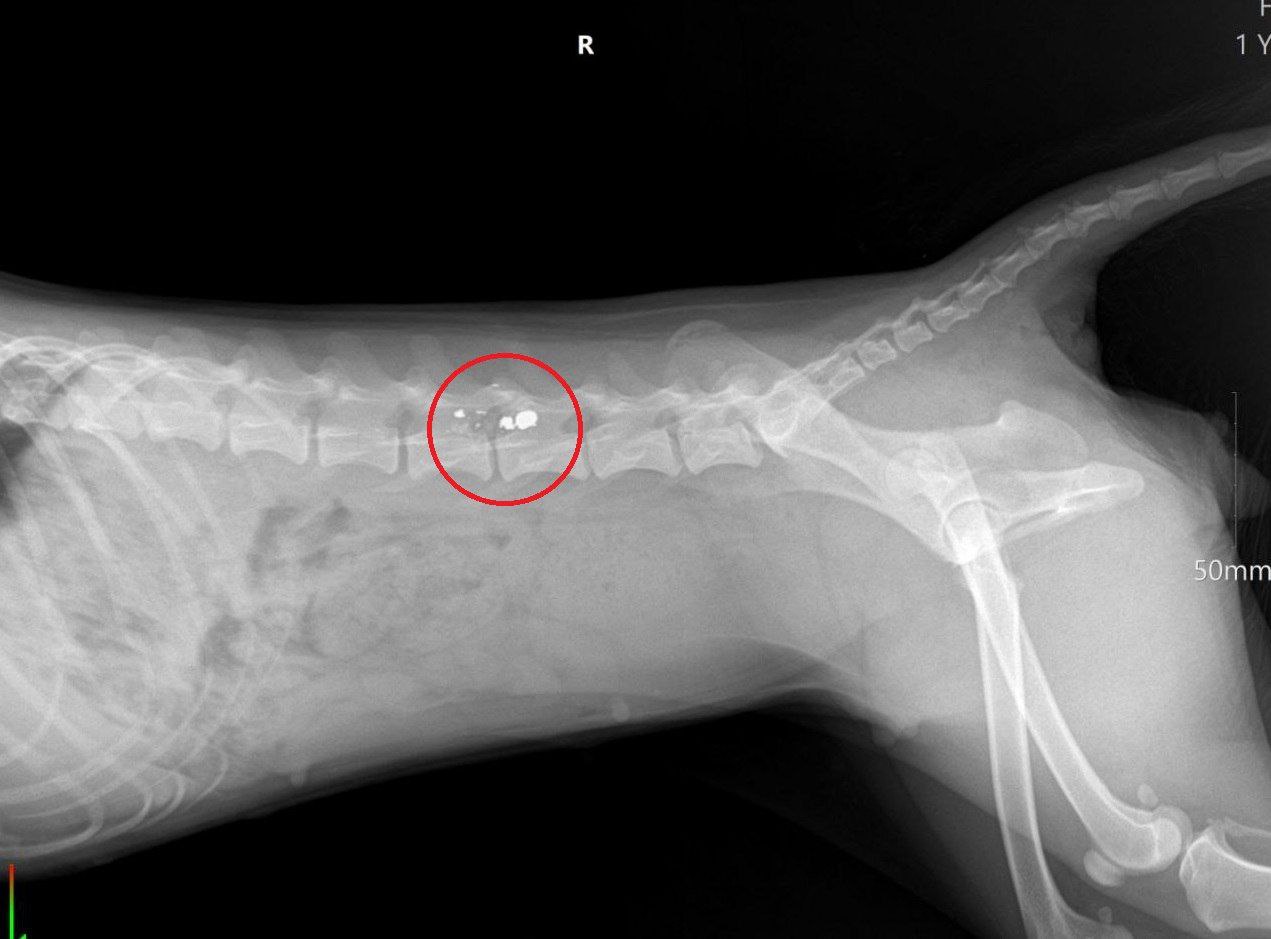

Собаку доставили в ветеринарную клинику. К сожалению, врачи диагностировали у домашнего любимца травмы, которые привели к параличу тазовых конечностей.